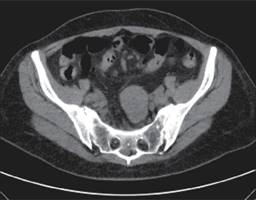

La tomografía axial computada (TAC) revela tumoración estenosante e infiltrante de las paredes del íleon con lumen estrecho y distensión de asas intestinales (Figuras 2 y 3).

Figura 3: Tomografía axial computada (TAC) con dilatación de asas de intestino delgado, con niveles, sugestivo de obstrucción intestinal.